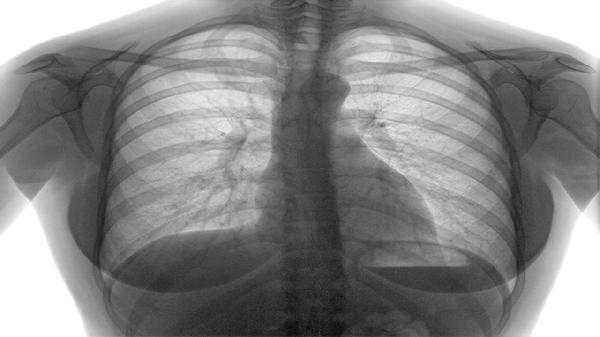

慢阻肺是一種以持續(xù)氣流受限為特征的慢性氣道炎癥性疾病,主要癥狀包括慢性咳嗽、咳痰、活動后氣短或呼吸困難。

活動后氣短或呼吸困難是慢阻肺的標(biāo)志性癥狀,早期僅在勞力時出現(xiàn),之后逐漸加重,以致在日?;顒由踔列菹r也感到氣促。這主要是由于氣道壁增厚、管腔狹窄、彈性回縮力下降以及肺泡結(jié)構(gòu)破壞導(dǎo)致氣體交換面積減少所致。呼吸困難會嚴(yán)重影響患者的活動能力和生活質(zhì)量。管理此癥狀的核心是長期堅持規(guī)范治療以延緩肺功能下降。患者需遵醫(yī)囑規(guī)律使用長效支氣管舒張劑,如噻托溴銨粉吸入劑、茚達(dá)特羅格隆溴銨吸入粉霧劑,必要時聯(lián)合吸入糖皮質(zhì)激素。此外,在專業(yè)指導(dǎo)下進(jìn)行肺康復(fù)訓(xùn)練,如縮唇呼吸、腹式呼吸及循序漸進(jìn)的耐力鍛煉,有助于改善呼吸肌功能,提高運(yùn)動耐力。